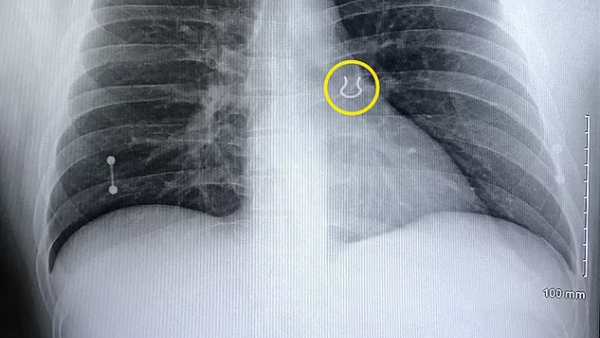

தொடர்ந்து இருமிக்கொண்டே இருந்தேன். எனது முதுகுப்பகுதியில் கடுமையான வலியை உணரத்தொடங்கினேன். நமது மூச்சுக்குழாயில் ஏதோ அடைப்பு ஏற்பட்டது போல உணர்ந்தேன். உடல் நிலை சரியில்லை என்று கருதியதால் மருத்துவரிடம் சென்றேன். அங்கு எக்ஸ்-ரே எடுத்து பார்த்ததில் 0.6 இன்ச் அளவு கொண்ட நோஸ் ரிங் நுரையீரலின் இடது மேல் பகுதியில் இருந்ததாக மருத்துவர்கள் கூறினர். முதலில் மருத்துவர் இதை கூறும் போது கேலி செய்கிறார் என்றே நான் கருதினேன்'' என்றார்.

அதிர்ஷ்டவசமாக நுரையீரலில் வேறு ஏதேனும் பெரிய ஆபத்து ஏற்படவில்லை என்று மருத்துவர்கள் தெரிவித்தனர். தன்னை சந்திக்க வரும் நண்பர்களிடம் இந்த சம்பவத்தை கூறினால் யாரும் நம்ப மறுக்கின்றனராம். இதற்காகவே மருத்துவர்கள் அளித்த எக்ஸ்-ரேவை ஆதாரமாக வைத்துக்கொண்டு இருப்பதாக லிகின்ஸ் கூறி வருகிறார். அதேபோல், நுரையீரலில் இருந்து நோஸ் ரிங் அறுவை சிகிச்சை எடுக்கப்பட்ட புகைப்படங்களையும் தன்னுடனே வைத்துக்கொண்டு அலையும் லிகின்ஸ், இனிமேல் நோஸ் ரிங் பக்கமே போகமாட்டேன் என்று சபதம் போடாத குறையாக சொல்லி வருகிறார்.